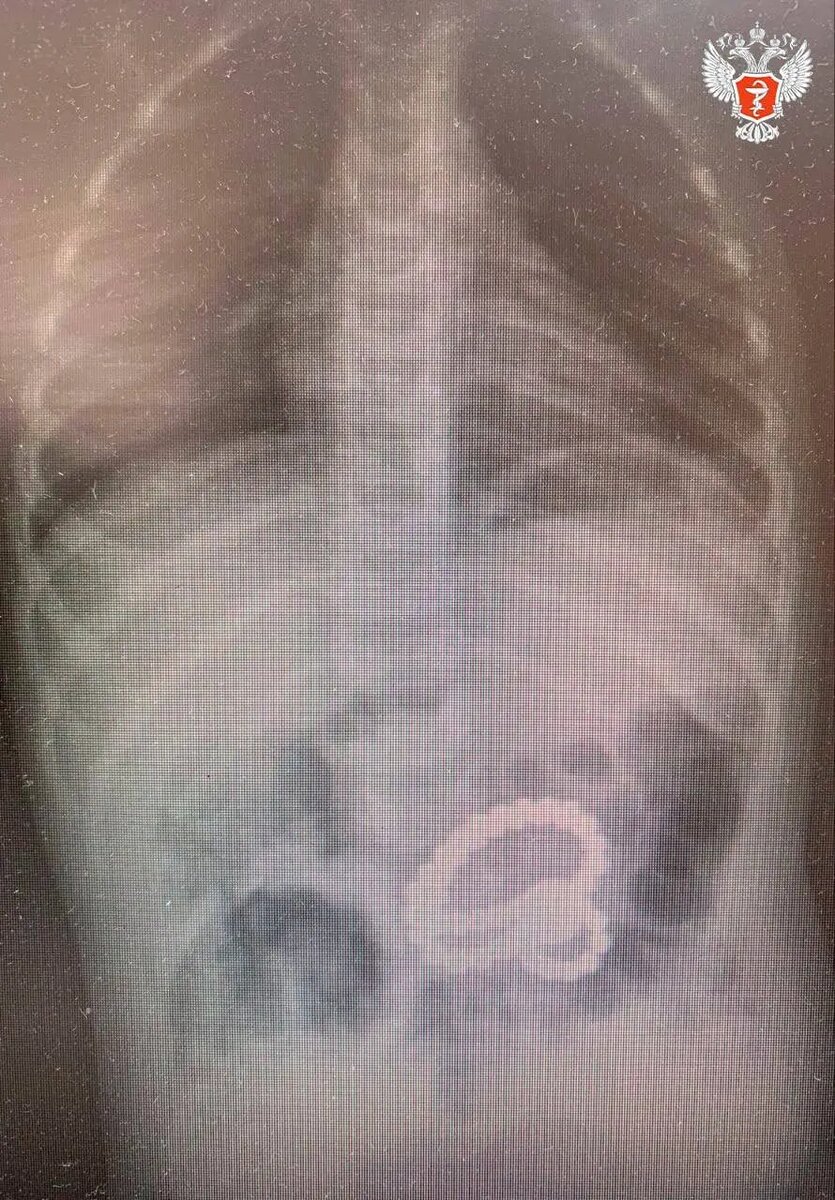

Маленький житель Воронежа проглотил почти пять десятков магнитных шариков и попал на операционный стол.

Фото: Минздрав Воронежской области

2-летний малыш поступил в Областную детскую клиническую больницу №2, где при обследовании желудка была обнаружена цепочка из более чем 40 магнитов. В ходе гастроскопии из маленького пациента последовательно извлекли 45 маленьких металлических шариков и один большой.

При этом еще три магнита остались внутри, извлечь их с помощью эндоскопа было невозможно. Медики удалили их через маленький разрез в брюшной стенке, рассказали в Минздраве Воронежской области.

Мальчик глотал магниты в разное время. Некоторые из них уже успели попасть в кишечник. Двигаясь по ЖКТ, магниты прицепились друг к другу и стянули стенки желудка и кишечника.